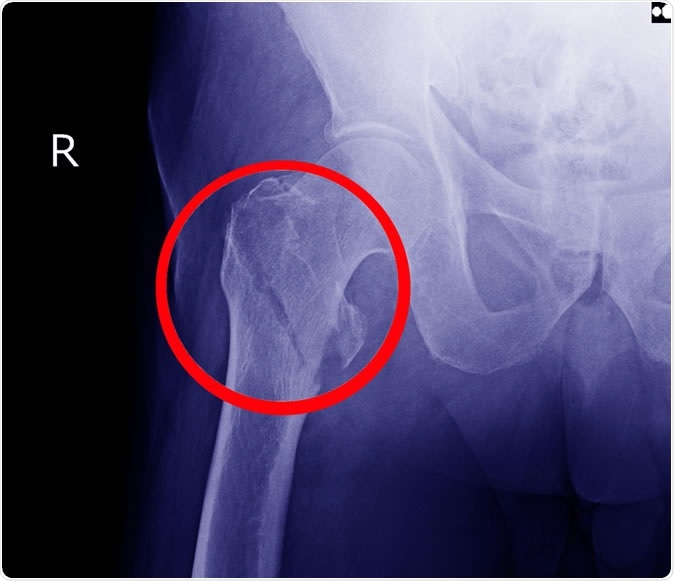

Hip fracture X-ray. Image redit: Richman Photo / Shutterstock

About 1.5 million American women break a bone every year, with about 14% of these breaks involving the hip joint. The resulting disease is associated with costs totaling $12.7 billion in health care. Moreover, up to one in five elderly women eventually die of complications following a hip fracture.